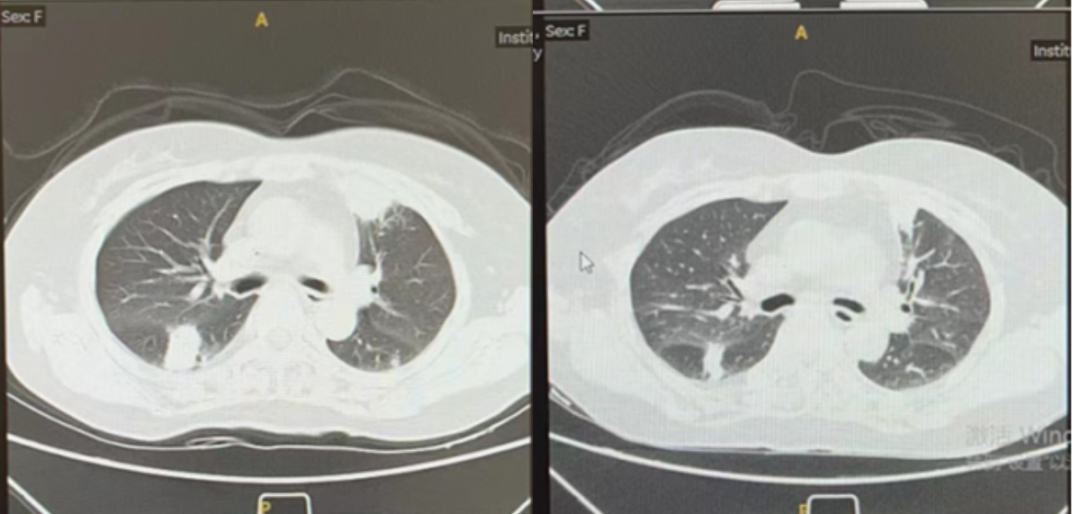

图5.治疗前后胸部CT影像

(左:24-03-14化疗前;右:24-06-03两次化疗后)

24-06-03复查胸部CT,肺部炎症病灶部分吸收改善。24-06-14复查骨髓常规CR,MRD转阴。渡过粒缺期后,停用L-AmB,序贯使用艾沙康唑(口服)进行抗真菌感染治疗

本资料报道一例AML患者IPA的诊疗过程。资料显示患者外院AML化疗期间发生真菌感染,初次经抗真菌药物治疗后症状缓解,后续化疗期间再次发生乏力、咳嗽、咯血等症状,使用卡泊芬净治疗效果不佳。外院查肺泡灌洗液NGS发现黄曲霉,先后予艾沙康唑(口服)和伏立康唑(口服)治疗无法耐受。入院后查曲霉半乳甘露聚糖抗原指数,结合现病史明确IPA诊断,予L-AmB(静脉)进行抗真菌治疗。L-AmB治疗期间耐受性良好,肌酐、血钾均未发生明显不良反应,肺部炎症病灶改善,获得较为理想的抗真菌治疗效果。